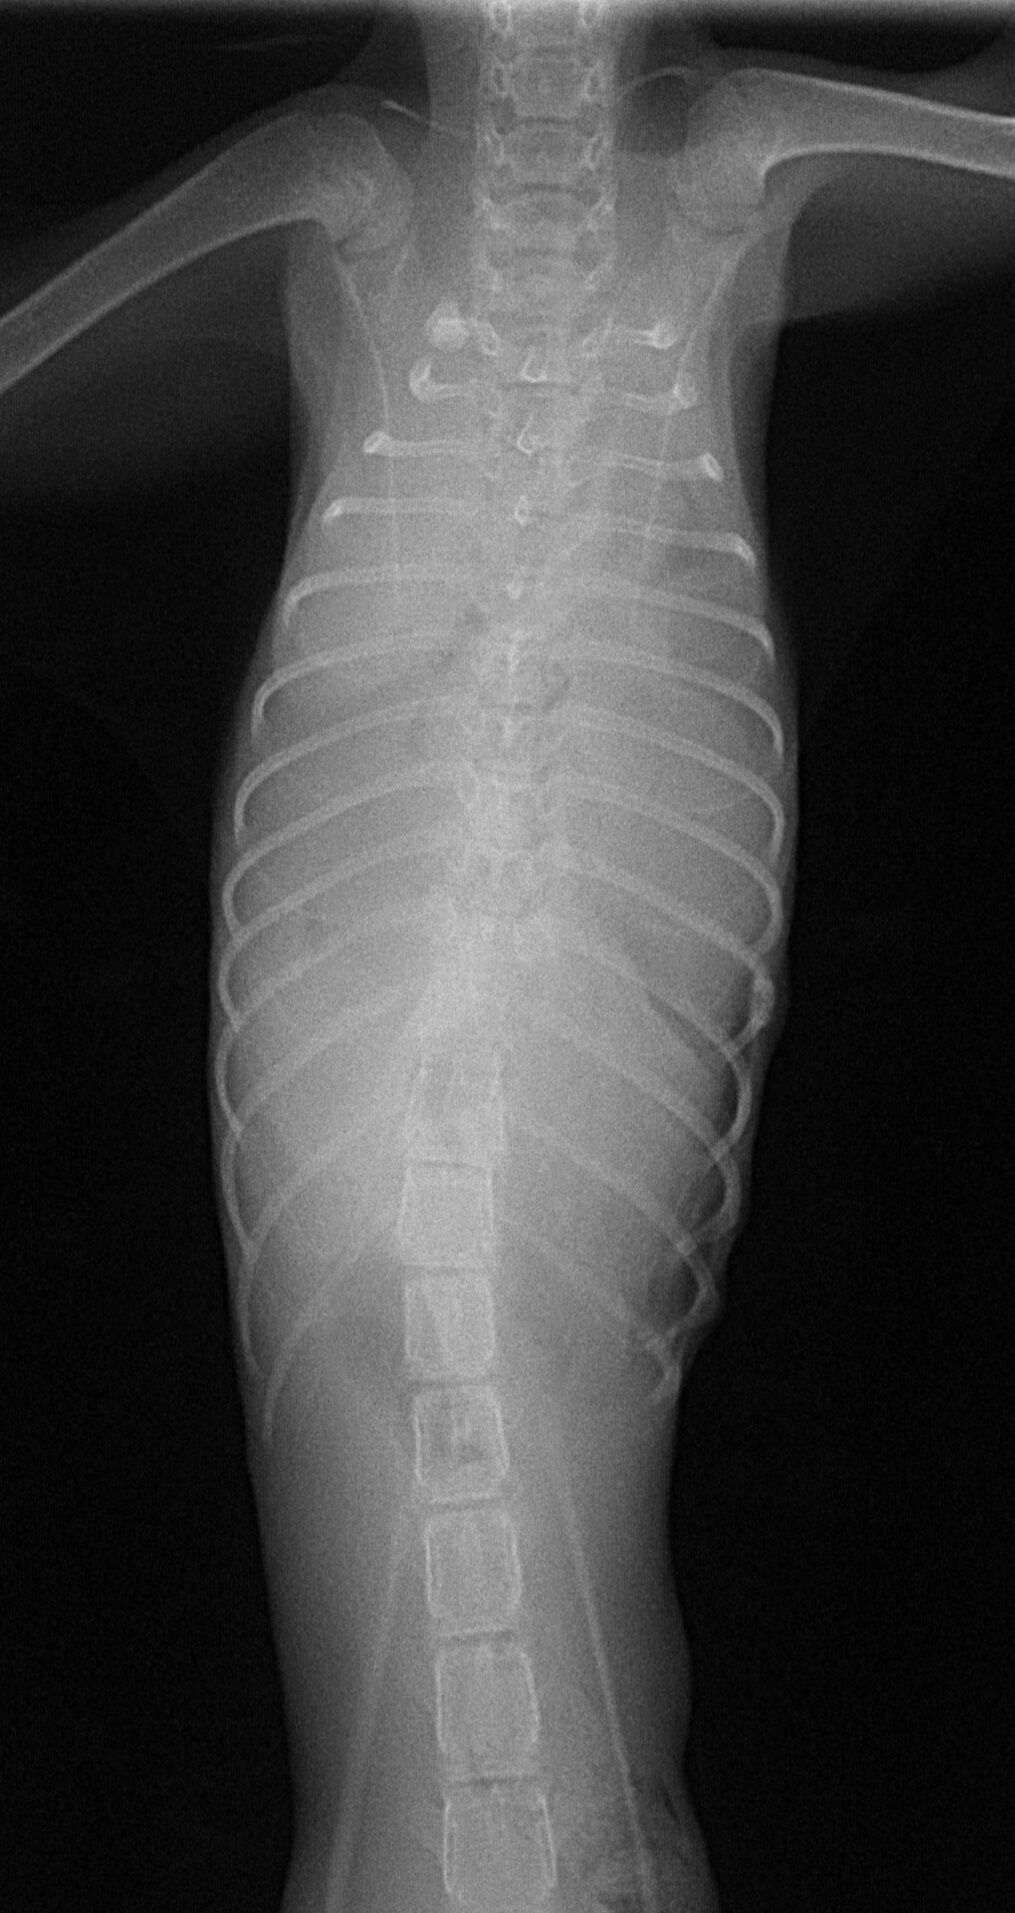

お久しぶりです。久々の症例報告です。12月中旬の日曜日に新規の飼い主さんから電話をいただきました。当院の近くの動物病院で診てもらっていたが手術ができないと言われたという。子猫が横隔膜ヘルニアになって死にそうになっているので、何とか手術ができないか、ということでした。すぐに連れてきていただきました。診れば体重は1㎏未満で、呼吸が浅くて体温もかなり低く、危険な状態でした。すぐにレントゲンを撮りました。それが以下の写真です。

胸部にあるはずの肺は、腹部の臓器である肝臓や胃、腸に押しつぶされている状態でした。こうなると肺を膨らませることができず、常に酸欠状態になります。すぐにICUに入れ呼吸を助けてあげました。少し落ち着いた状態になりました。血液検査で状態を把握し、それに応じて点滴をし、その夜に手術する予定にしました。